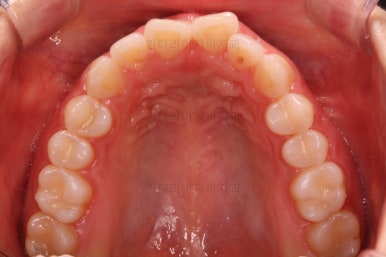

부산나비앞니교정 키다리아저씨치과에 처음 내원하셨을 당시의 입 안 모습입ㄴ디ㅏ.

보시다시피 위아래 정중앙에 있는 치아가 V자 형태로 꺾여있었어요.

흔히 "나비치아", "나비앞니"라고 표현을 하는데 나비 날개짓을 하듯이 꺾여 있다고 그렇게 부릅니다.

미관상 약간 보기 싫은 것도 있지만 앞니쪽이 삐뚤하게 되면 치석이 더 잘생기고 잇몸에 염증이 오기도 쉬워요.

당연히 가지런하게 해주는게 훨씬 도움이 된답니다.

어금니쪽의 맞물림은 굉장히 양호한 편이였기 때문에 부분교정에 딱 알맞는 경우였어요.